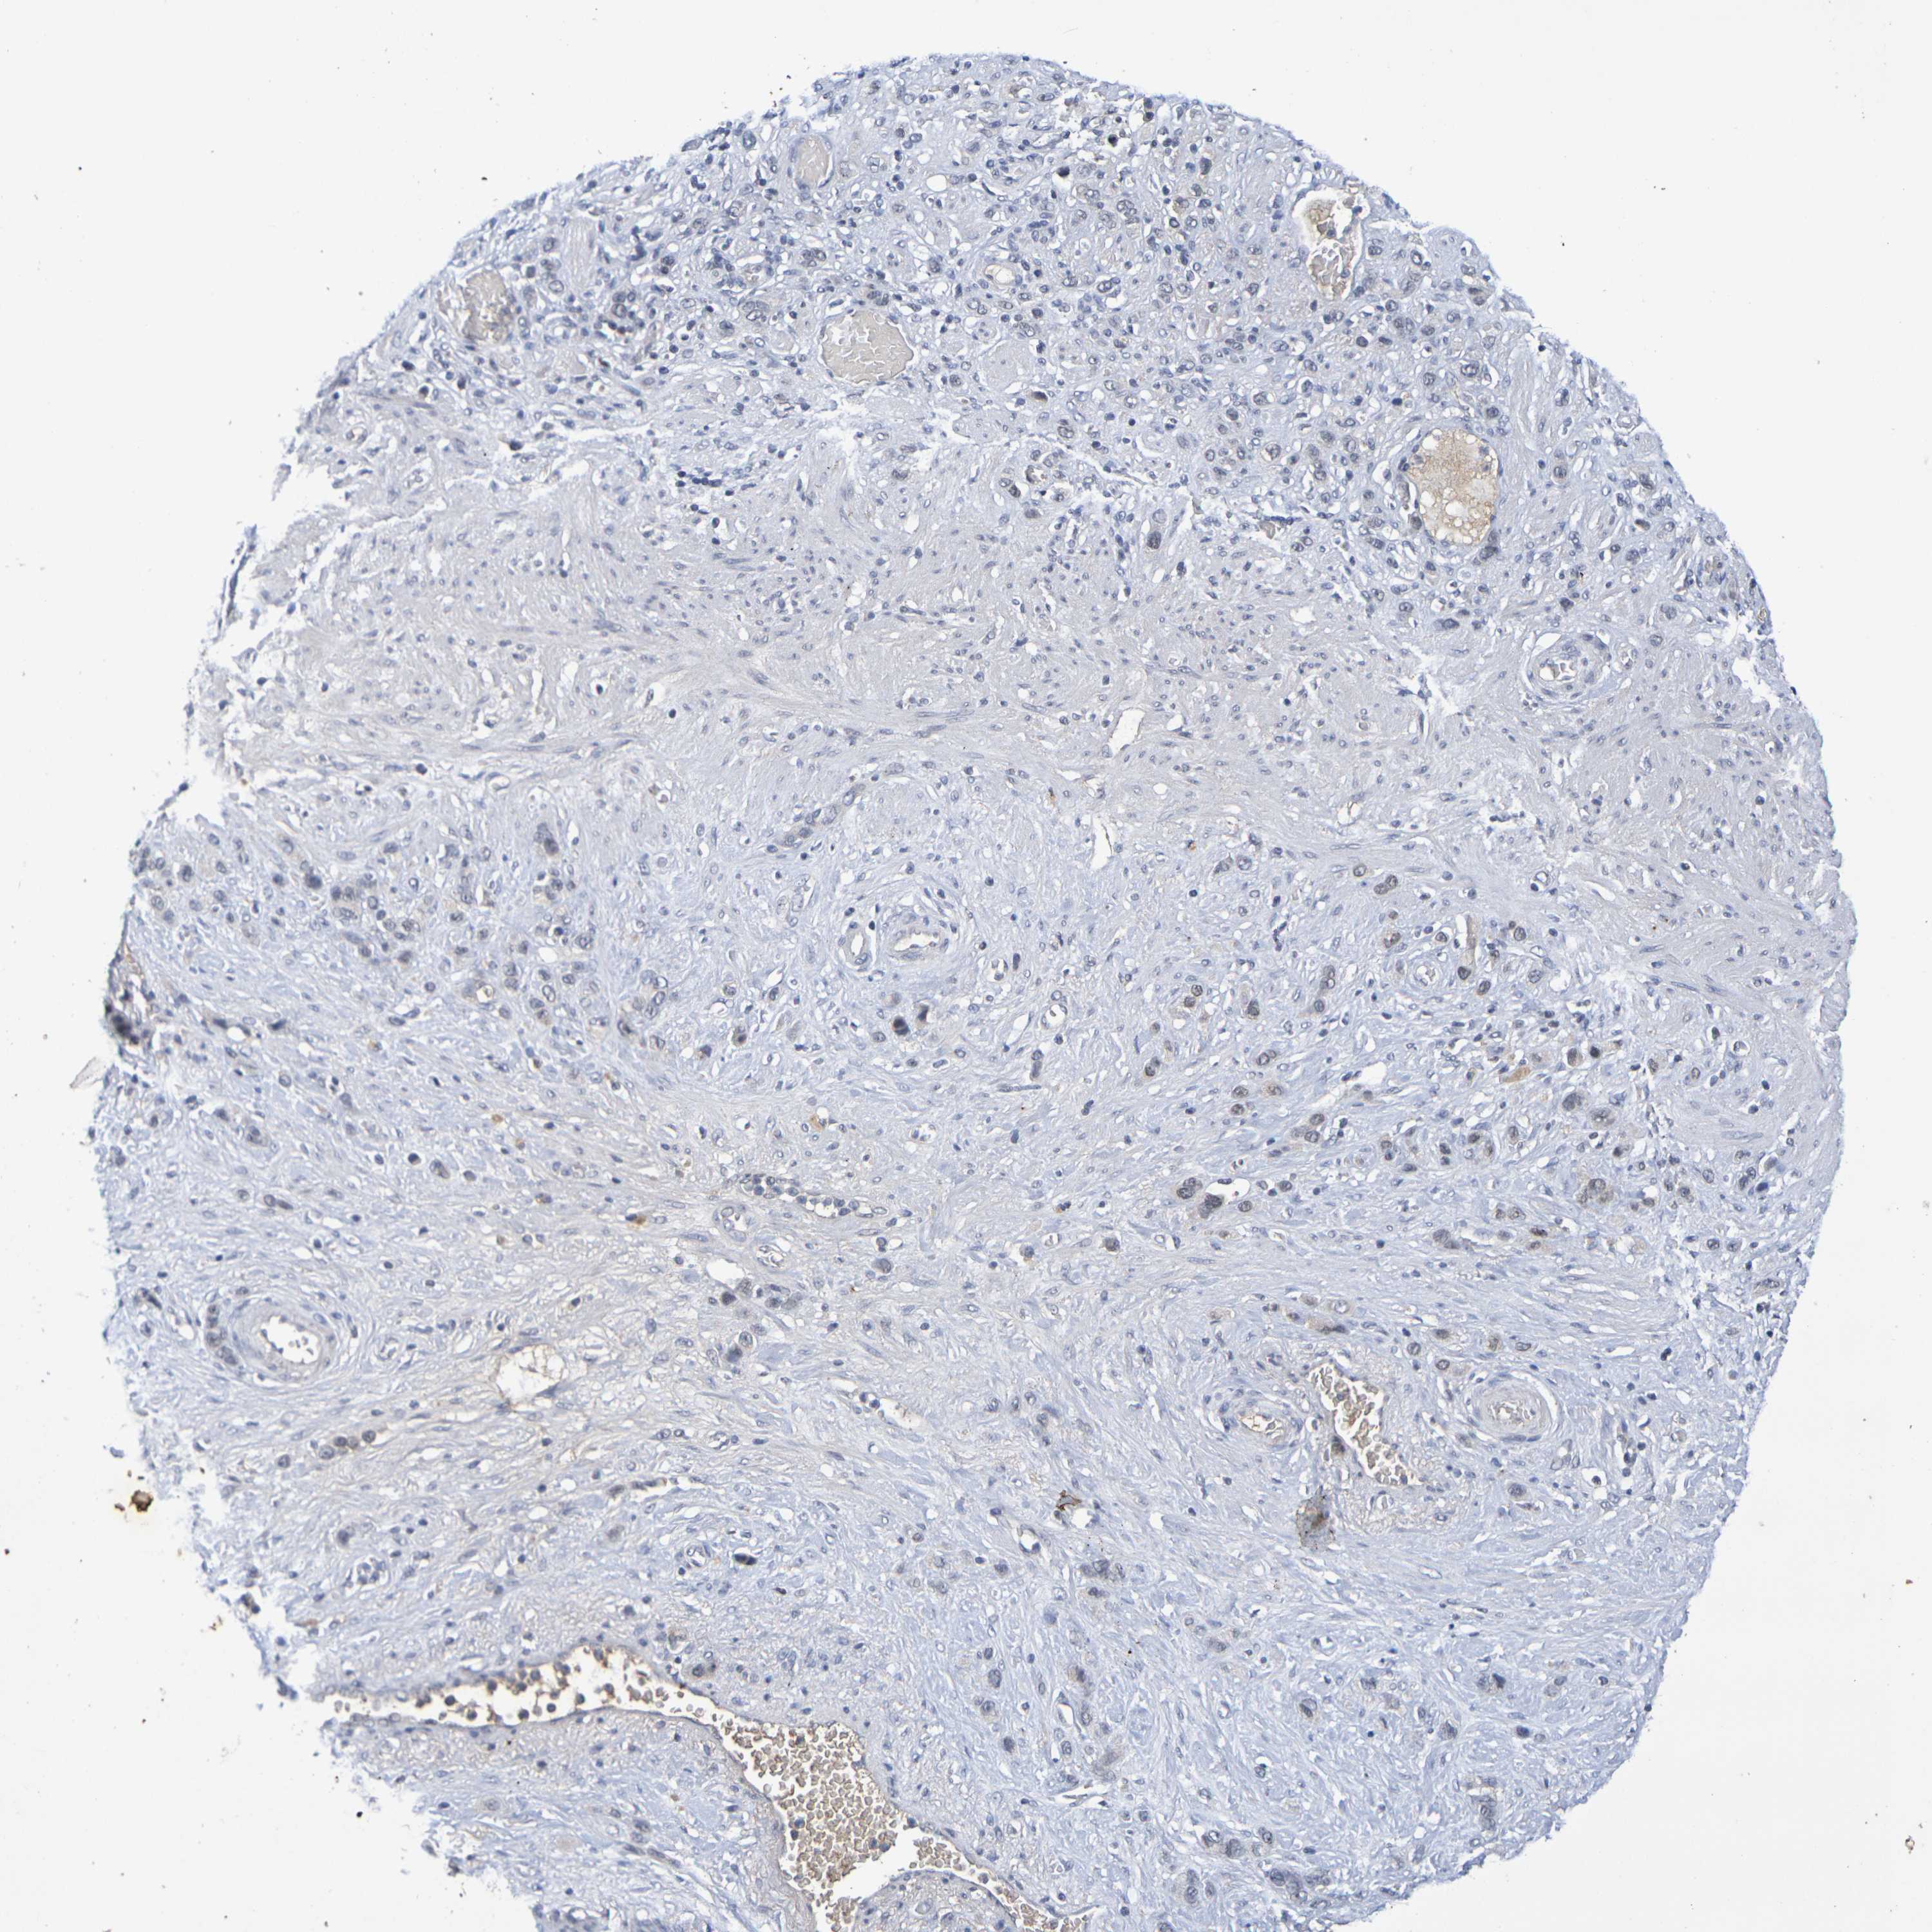

STOMACH CANCER - Protein expressioni

A mouse-over function shows sample information and annotation data. Click on an image to view it in a full screen mode. Samples can be filtered based on level of antibody staining by selecting one or several of the following categories: high, medium, low and not detected. The assay and annotation is described here.

Note that samples used for immunohistochemistry by the Human Protein Atlas do not correspond to samples in the TCGA dataset.

Antibody stainingi

Antibody staining in the annotated cell types in the current human tissue is reported as not detected, low, medium, or high, based on conventional immunohistochemistry profiling in selected tissues. This score is based on the combination of the staining intensity and fraction of stained cells.

Each image is clickable and will lead to virtual microscopy that enables deeper exploration of all samples and also displays staining intensity scores, fraction scores and subcellular localization as well as patient and tissue information for each sample.

Antibody HPA001907

Antibody HPA002735

Antibody CAB010451

Antibody CAB080271

Staining

High

Medium

Low

Not detected

Intensity

Strong

Moderate

Weak

Negative

Quantity

>75%

75%-25%

<25%

None

Location

Nuclear

Cytoplasmic/membranous

Cytoplasmic/membranous,nuclear

Adenocarcinoma, NOS

Adenocarcinoma, High grade